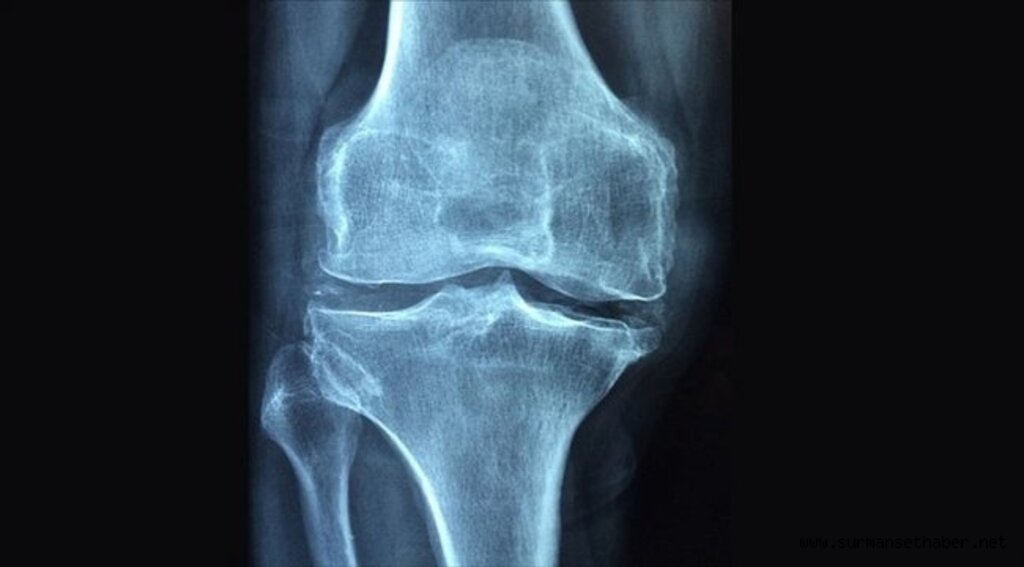

Gazi Üniversitesi Tıp Fakültesi Fizik Tedavi ve Rehabilitasyon Anabilim Dalı Öğretim Üyesi Prof. Dr. Zafer Günendi, AA muhabirine, en sık görülen kemik hastalığı olan osteoporozun gelişiminde romatizmal hastalıkların etkisine ilişkin açıklamalarda bulundu.Romatizmal hastalıkların, en çok kas iskelet sistemi ve ardından diğer organları tuttuğunu, tuttuğu bölgelerde de hasara bağlı fonksiyonel bozukluklara sebep veren iltihabi bir rahatsızlık olduğunu dile getiren Günendi, 100'den fazla romatizmal hastalık tanımlandığını söyledi. Günendi, bunlardan bazılarının sık, bazılarının ise nadir görüldüğünü ve romatizmal hastalıkların nedeninin tam olarak bilinmediğini vurguladı.Romatizmal hastalıklar içinde en sık "romatoid artrit" ve "ankilozan spondilit"in görüldüğünü aktaran Günendi, şunları kaydetti:"Bu sık görülen romatizmal hastalıklar, yaklaşık 100 erişkinden birinde gelişebilmektedir. Düzgün takip ve tedavi edilmeyen romatizmal hastalıklar, kişinin kas-iskelet gibi organ sistemlerinde hasara neden olarak fonksiyonları bozmakta, aynı zamanda altta yatan iltihabi süreç kalp-damar hastalıklarının da daha erken ve daha sık görülmesine neden olarak yaşam beklentisini de kısaltmaktadır. Dolayısıyla artan iş gücü kaybı, sağlık bakım maliyetleri gibi durumlar, toplum sağlığını da etkilemektedir."Romatizmal hastalıkların aynı zamanda osteoporoz gelişimi için de bir risk faktörü olduğunu vurgulayan Günendi, "Yapılan çalışmalarda iltihabi romatizmal hastalığı olanlarda, aynı yaş ve cinsiyetteki sağlıklı kişilere göre osteoporoz görülme sıklığının arttığı gösterilmiştir." dedi.Osteoporoz ve osteoporoza bağlı kırıkların, romatizmal hastalığın kişiye ve topluma getirdiği yükün daha da artmasına neden olduğunu dile getiren Günendi, "Bu nedenlerle romatizmal hastalıklı kişilerde osteoporoz gelişiminin daha sık olabileceği unutulmamalı, diyet ve egzersiz gibi önleme girişimleri, uygun tarama yöntemleriyle erken tanı ve gerekiyorsa tedavi girişimleri yürütülmeli." ifadelerini kullandı."İltihap, bağışıklık sistemini bozuyor"

"Romatizmal hastalıklarda osteoporoz gelişiminde en önemli neden, altta yatan iltihaptır." bilgisini veren Prof. Dr. Günendi, iltihabın gelişimi aşamasında bağışıklık sisteminin de bozulduğunu söyledi.Bağışıklık sisteminde, hücreler arası etkileşimi sağlayan sitokin adı verilen protein yapıların olduğunu anlatan Günendi, "Bunların bazıları iltihabı tetiklerken bazıları da iltihap gelişimini önlemektedir. Sağlıklı kişilerde sitokinler denge içinde bulunurken, romatizmal hastalığı olan bireylerde sitokin dengesi, iltihabı tetikleyen sitokinlere doğru kaymaktadır. Romatizmal hastalıklarda artmış iltihap tetikleyici sitokinler, aynı zamanda kemik yıkımını da hızlandırmaktadır." diye konuştu."Kalsiyumdan zengin beslenilmeli"

Romatizmal hastalıklarda osteoporoz sıklık artışının başka bir nedeninin de hareketsizlik olduğuna işaret eden Günendi, şöyle devam etti:"Romatizmal hastalığa sahip olan kişiler hastalığının aktif dönemlerinde mevcut iltihabı ve dolayısıyla ağrılarını arttırmamak için hareketliliklerini azaltmakta yani istirahat etmektedirler. Biliyoruz ki kemik yapımını uyaran önemli nedenlerden biri de kemiğe binen yüklenmedir. Bu da ayakta dik pozisyonda durmakla, hareket etmekle mümkün olmaktadır. Hareketsiz kalmak da kemik üzerine binen yükün azalmasına ve kemik yıkım hızının artmasına neden olacaktır."Romatizmal hastalıklarda osteoporoz gelişimini önlemek için, romatizmal hastalığın iyi bir şekilde tedavi edilmesinin yanında, genel osteoporozdan koruyucu önlemlerin de uygulanması gerektiğini belirten Günendi, sözlerini şöyle tamamladı:"Yani hastanın kalsiyumdan zengin beslenmesini önermek, diyetle kalsiyum alımı yetersizse kalsiyum desteği sağlamak, kalsiyum metabolizmasında önemli bir hormon olan D vitamin düzeylerini uygun sınırlar arasında tutmak, yürüyüş gibi aerobik egzersizler ve hastalık aktivitesini arttırmayacak ölçüde kas kuvvetlendirici egzersizleri düzenli yapmasını sağlamak gerekmektedir."